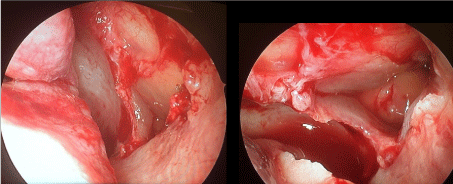

The patient underwent endoscopic middle meatal antrostomy on the left side under general anaesthesia. Careful dissection of the lateralized uncinate process was done to avoid injury to the globe. Thick mucoid discharge was suctioned out from the maxillary sinus (Figure 2). A wide antrostomy was done to ventilate the sinus. Prolapsed globe was seen through the antrostomy (Figure 3A and Figure 3B).

Figure 2: Thick mucoid discharge seen from the maxillary sinus following uncinectomy. View Figure 2